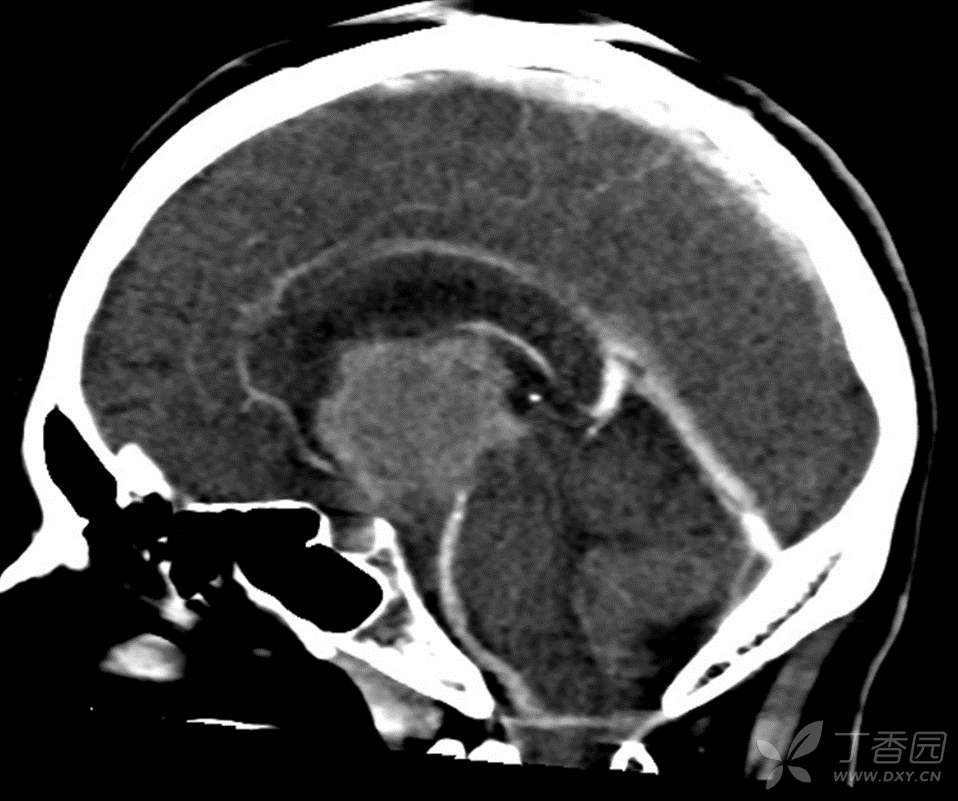

男,44岁,记忆力下降、乏力5月余,多尿3月余,CTMR全,疑难病例,能正确诊断吗?

图像不多,能诊断正确吗?有特征性吗?